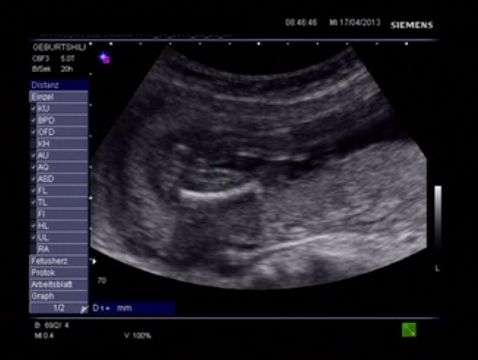

Hello Everyone! Its me again :-) A Gender swaying friend (wanting a Girl) made the The Baby Gender Predictor Test: Am I having a boy or girl? DNA - Test And it said -> BOY! Her second son is 19 Months old and she was pretty careful making the test... Now she went to her doctor’s appointment and the doctor was sure it’s a Girl!! What do you think? Picture 1 : (NT-Scan – Baby Nr.3 -> Is the current pregnancy ) Sohnemann 2 is her second Boy ;-) Picture 2: 17 weeks pregnant potty scan the arrow should show the girl parts .... So Ladys what do you think any chance itīs a GIRL??? Greetings & Thanks ....

Attachment 10345